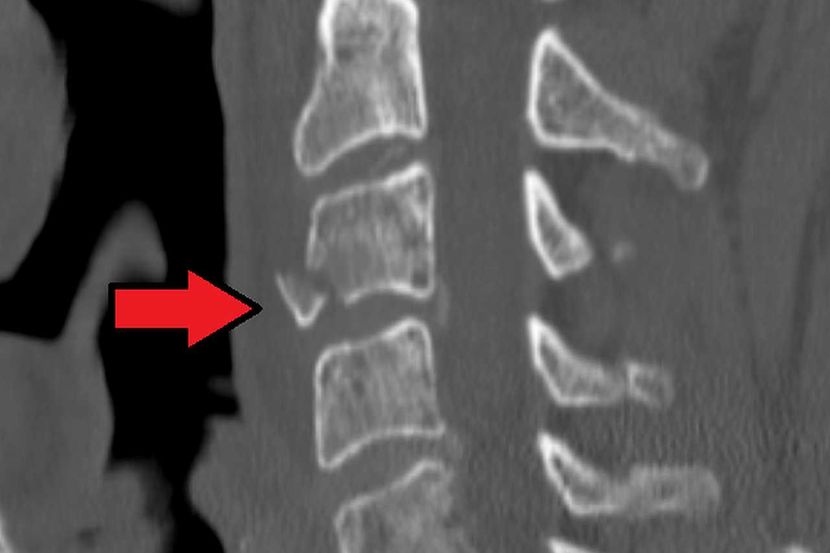

Električni pulsevi sa fizioterapijom mogu ublažiti paralizu nakon frakture vrata

Novi sistem, koji ne zahteva hirurgiju, takođe je njihov prvi pokušaj da pronađu tretman za ljude sa frakturom vrata, koji su izgubili pokretljivost ruku. Rezultat je da električna stimulacija sa fizioterapijom dovodi do neke ograničene obnove oštećenih živaca.